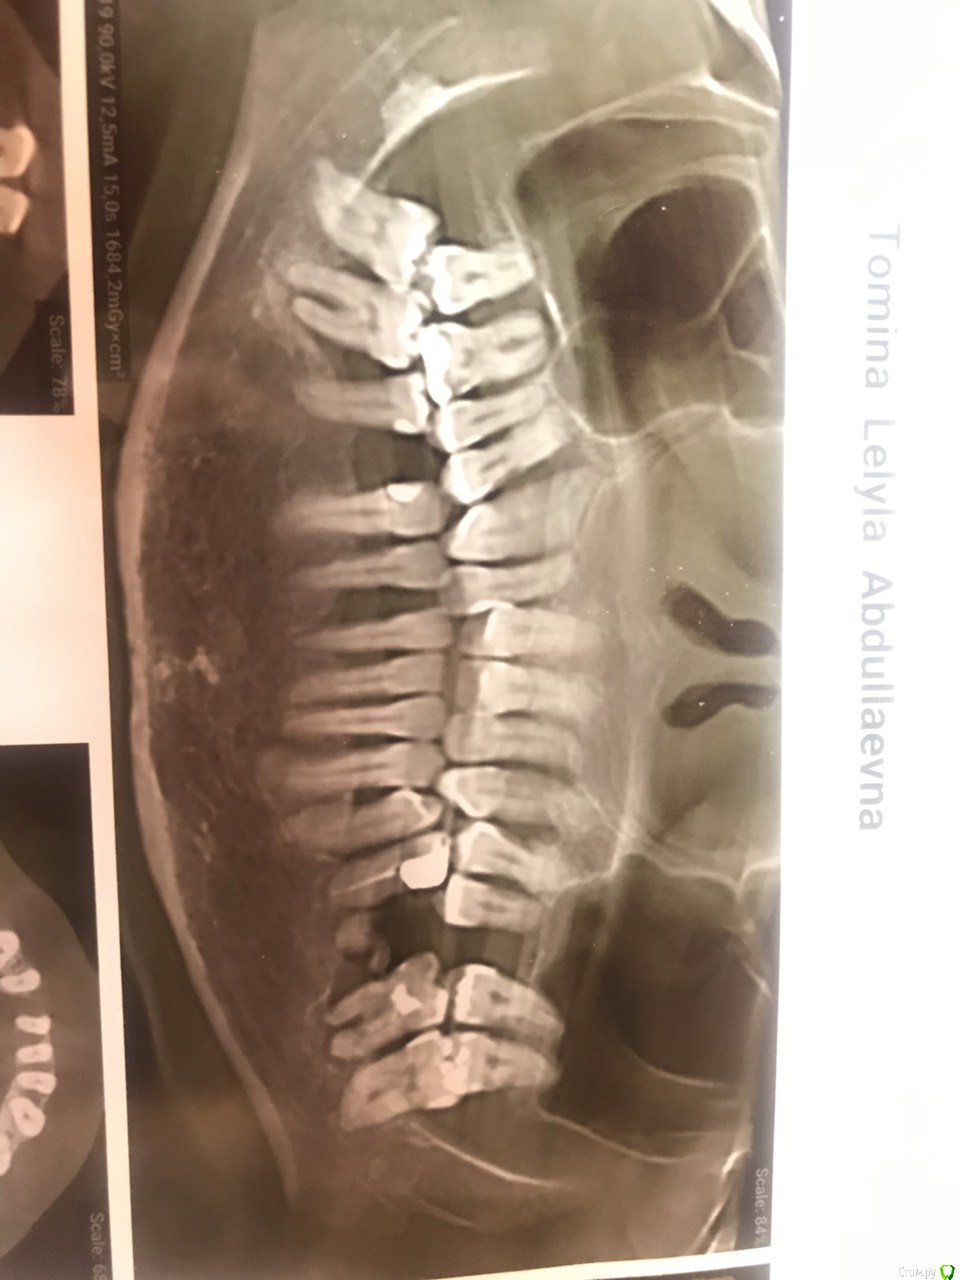

leyla-night Опубликовано 3 августа, 2019 Поделиться Опубликовано 3 августа, 2019 Добрый день! Очень нужен совет. Ходила в стоматологию к терапевту. сказали есть подвижность некоторых зубов. Сделали чистку. зубы стали остальные шататься, даже те которые не шатались, а один теперь болит, а я пришла у меня ничего не болела. Сказали сделать три Д снимок, сделала. Сообщили, что 7 зубов нужно удалять. Но заниматься мной не стали. Сказали, сами выпадут потом поставите челюсть. Я инвалид 1 группы не могу сидеть в кресле стоматолога. До 2013 года меня принимали в моей коляски и пломбы ставили и чистку делали все было нормально. Сейчас стоматологии стали еще лучше, но я не могу получить помощь. Посоветуете пожалуйста по моему снимку. можно, мне как то помочь., Ссылка на комментарий

hogsmeed Опубликовано 3 августа, 2019 Поделиться Опубликовано 3 августа, 2019 Здравствуйте Подвижность зубов после чистки обычное явление(вернее ощущение этой подвижности). По снимку действительно нужно убирать зубы, спасти их затруднительно, дальше либо имплантация, либо съемный протез). Принять пациента в коляске вообще не проблема, установки фирмы Adec например (довольно популярной фирмы) оборудованы подголовником, который позволяет лечить в вашем кресле. Ссылка на комментарий